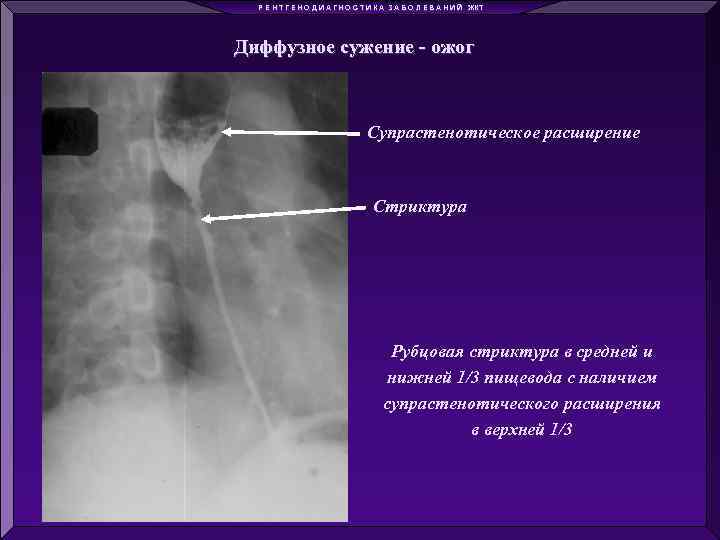

Р Е Н Т Г Е Н О Д И А Г Н О С Т И К А З А Б О Л Е В А Н И Й ЖКТ Диффузное сужение - ожог Локальное сужение - опухоль Диффузное расширение – ахалазия кардии Локальное расширение - дивертикулы

Р Е Н Т Г Е Н О Д И А Г Н О С Т И К А З А Б О Л Е В А Н И Й ЖКТ Диффузное сужение - ожог Локальное сужение - опухоль Диффузное расширение – ахалазия кардии Локальное расширение - дивертикулы

Р Е Н Т Г Е Н О Д И А Г Н О С Т И К А З А Б О Л Е В А Н И Й ЖКТ Диффузное сужение - ожог Супрастенотическое расширение Стриктура Рубцовая стриктура в средней и нижней 1/3 пищевода с наличием супрастенотического расширения в верхней 1/3

Р Е Н Т Г Е Н О Д И А Г Н О С Т И К А З А Б О Л Е В А Н И Й ЖКТ Диффузное сужение - ожог Супрастенотическое расширение Стриктура Рубцовая стриктура в средней и нижней 1/3 пищевода с наличием супрастенотического расширения в верхней 1/3